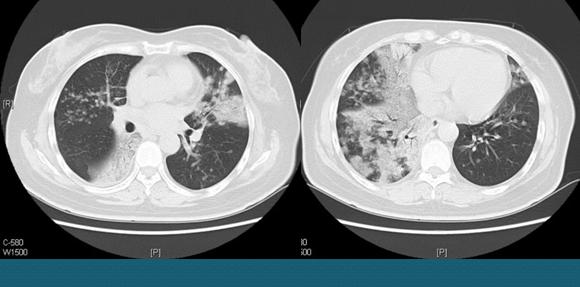

像这位女士,反复咳嗽、痰多半年多,一直忽视了痰液的报警信号,结果拖到晚期才到医院检查,癌细胞已经随着痰液发生了多发气道播散,双肺多发病灶,已经失去手术机会了。

中老年人要重视身体的每一种报警信号,短期不缓解时千万别硬抗,以免错过窗口期。